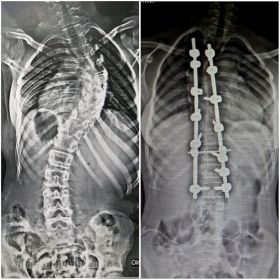

Chiropractic BioPhysics® or CBP® is the most peer-reviewed and published chiropractic technique in the world. It’s the most advanced, scientific, and proven chiropractic technique which corrects and restores your spine back to alignment, and in the process, alleviates pain and discomfort from its source.